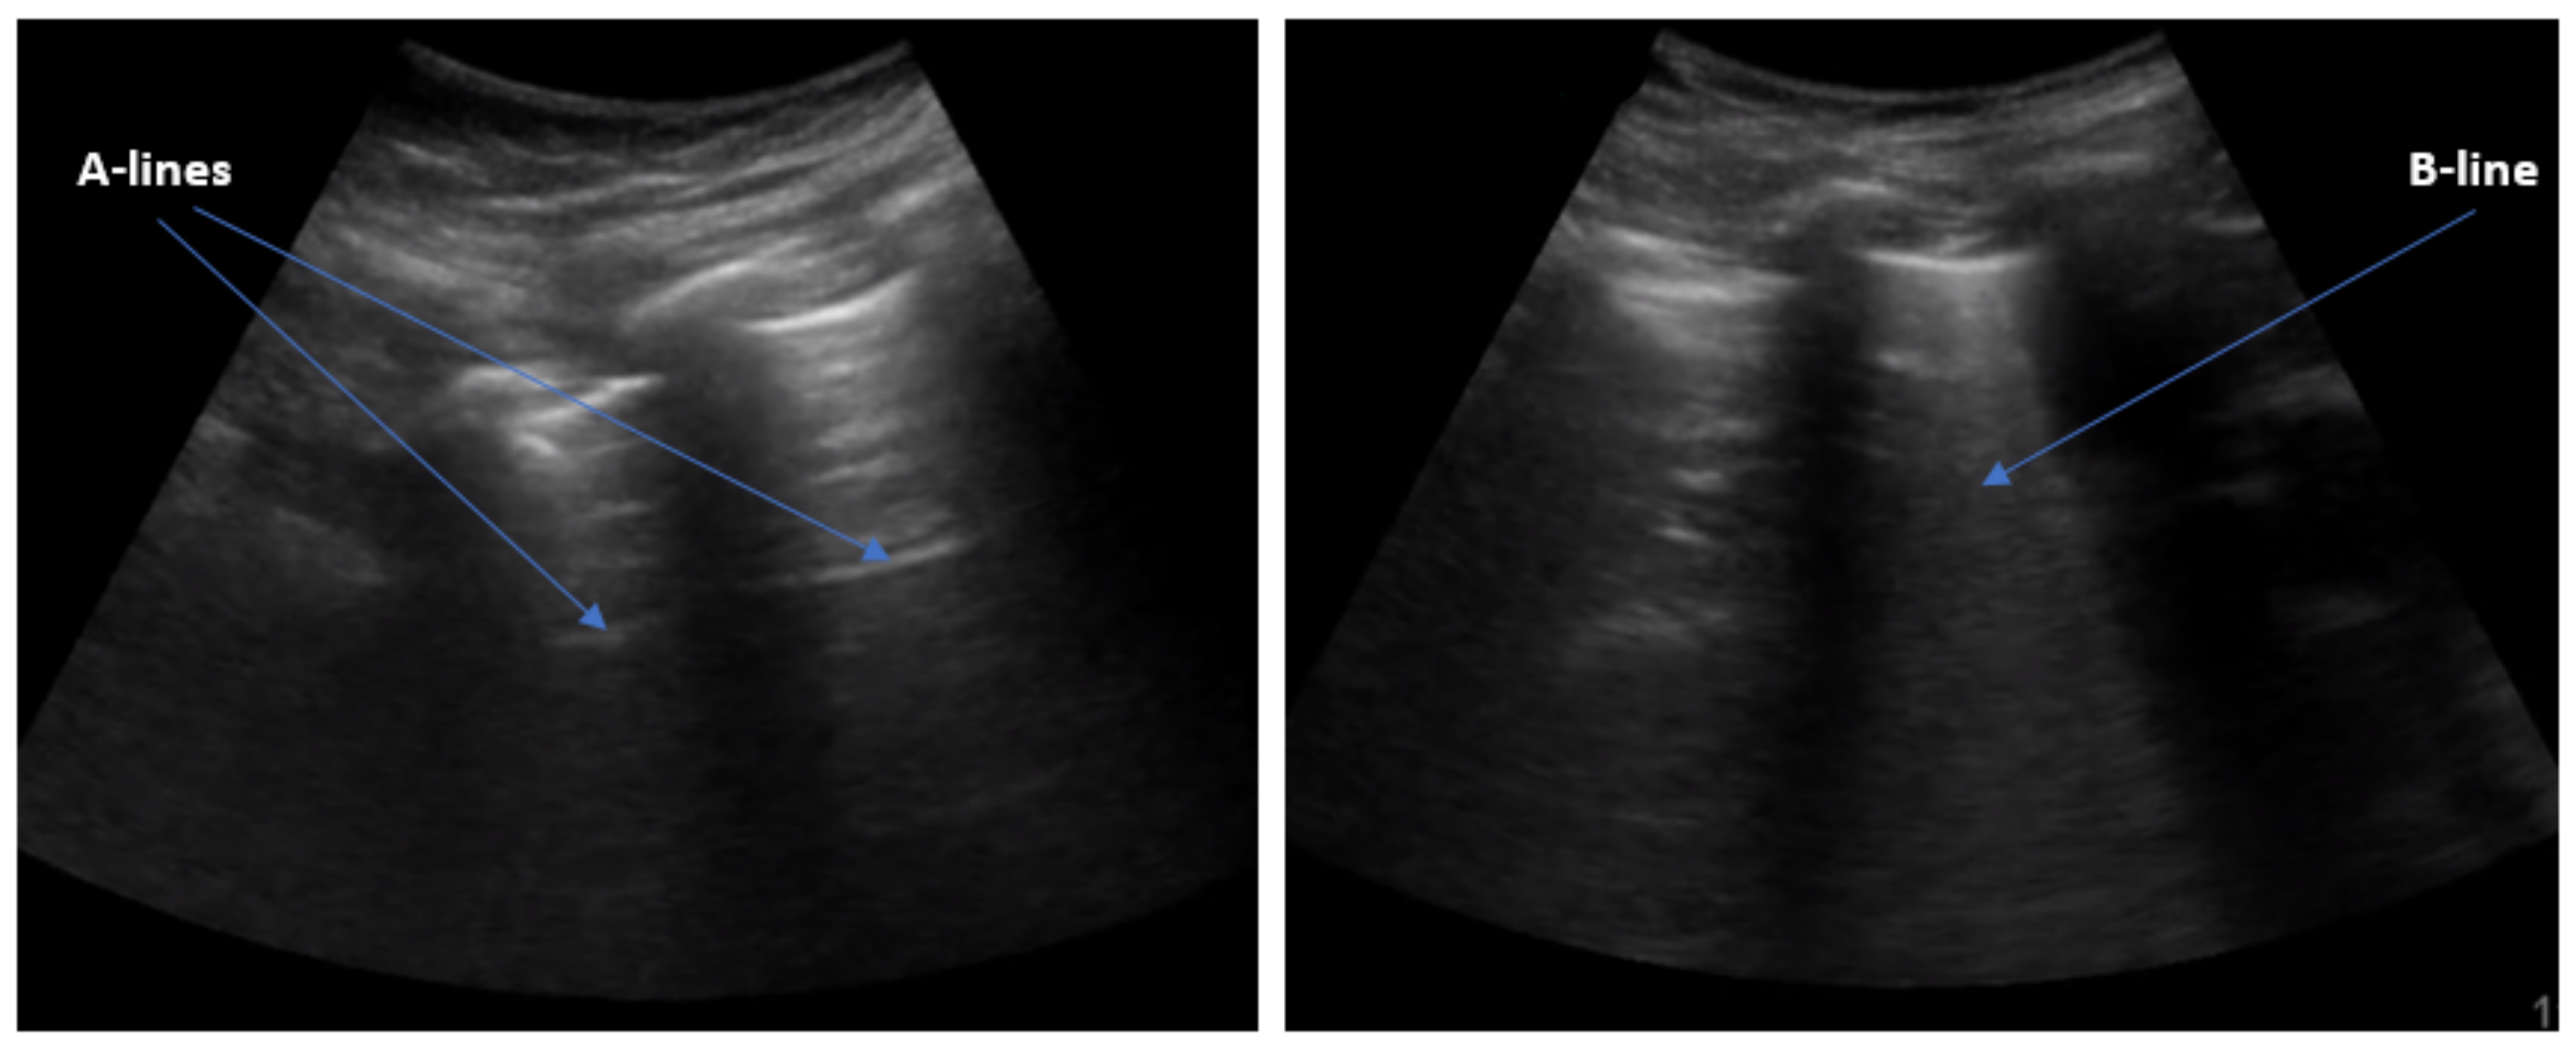

:1. Introduction